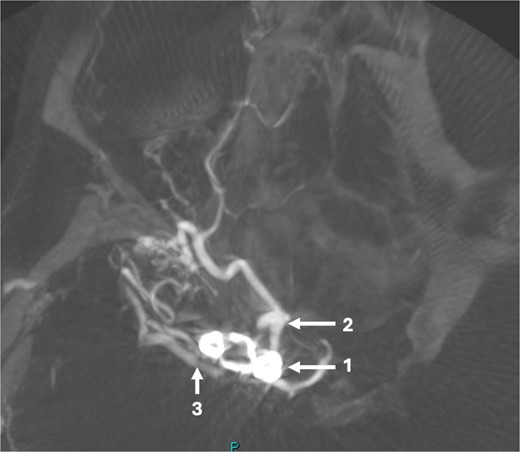

At 2 years, a follow-up CT angiogram was reassuring. After a symptom free period of 6 years after the initial operation, this patient started experiencing intermittent holocranial headaches, severe enough to necessitate presentation to Emergency Department. CT scans did not reveal any new abnormalities. In 2018, after multi-disciplinary discussion for the ongoing headaches, a digital subtraction angiogram (DSA) was offered to the patient to investigate the status of the clipped aneurysm and the untreated, unruptured posterior communicating (PCOM) aneurysm as a cause of her headaches.

The DSA showed significant narrowing of the ACA and complete occlusion of the MCA distal to the clipped and fully occluded aneurysm. The right recurrent artery of Heubner, arising from A1, was hypertrophied and supplying the medial lenticulostriate territory. There was diffuse small vessel formation in this same area (Fig. 3). This DSA suggested the progressive distal stenosis secondary to the surgical clip led to anastomotic collateral formation, consistent with a radiological and clinical Moyamoya phenomenon. Patient’s symptoms were managed conservatively. Subsequent CT angiogram in 2018, 2021, and 2023 showed no further progression of the Moyamoya phenomenon.